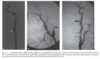

carotis stenosis measuring

The minimal lumen diameter is divided by the diameter of the distal ICA where the walls become parallel so as to avoid any post-stenosis dilatation

Carotid endarterectomy (1) **Asymptomatic** stenosis of 60–99% has a 6% absolute risk reduc- tion for stroke over 5 years if operative mortality < 3% and if the patient has a 5-year life expectancy (a) stroke risk of untreated asymptomatic stenosis is 2% per year (2) **Symptomatic stenosis** of 70–99% has a 17% absolute risk reduction for stroke over 2 years if operative mortality < 6% and if the patient has a 5-year life expectancy (a) Stroke risk of untreated symptomatic stenosis is 13% per year (b) Benefit of surgery persists for less than 1 year after stroke or TIA; therefore, surgery is best done as soon as possible after a stroke (usually within 4 to 6 weeks when the risk of stroke is highest) (c) 50%–70% symptomatic stenosis may also benefit from surgery in (i) Male patients (ii) Conjunction with plaque ulceration (iii) Cases involving nonlacunar hemispheric stroke or TIA (d) Endovascular stenting is a treatment option for carotid ste- nosis in patients who are poor surgical candidates